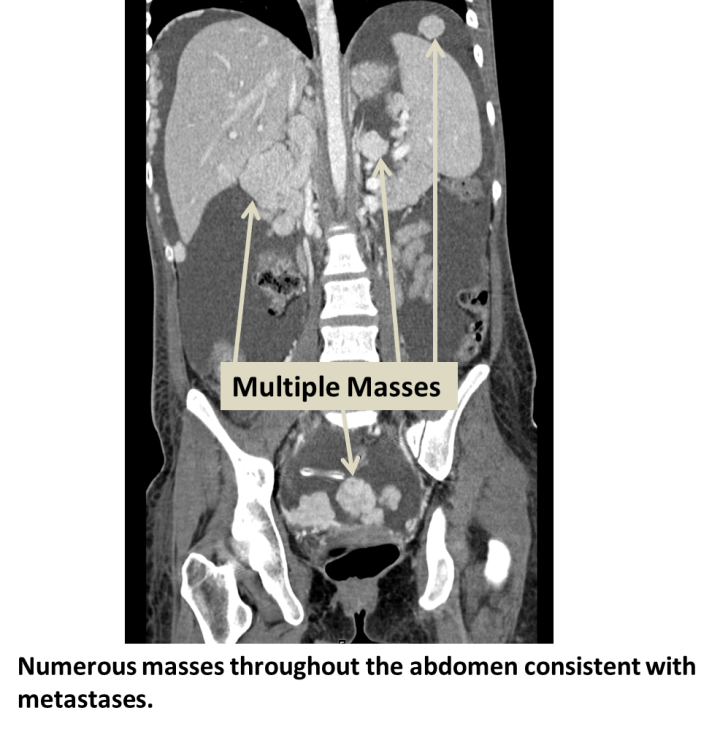

CT abdomen demonstrating liver metastases. Download Scientific Diagram How Long Do You Live With Liver Metastases A prognosis is the doctor’s best estimate of how cancer will affect. A person should get regular checkups to help ensure that they remain free of cancer. It depends on many things, including where the. There is no way of knowing exactly how long someone will live with liver metastases. The liver is a common site for metastases from many. How Long Do You Live With Liver Metastases.